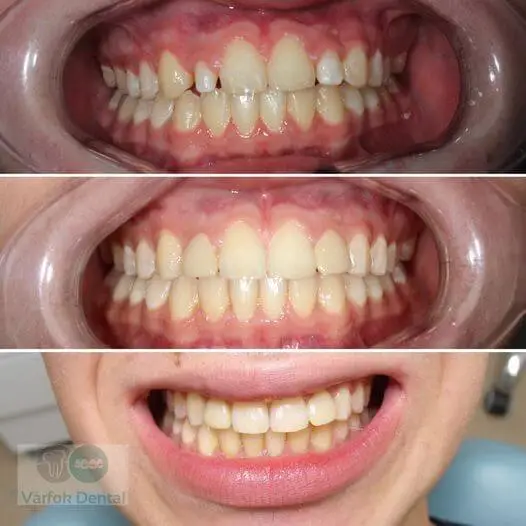

Fogszabályozás

Fiatal páciensünk elülső nyitott harapásának kezelésére első lépésként belső fogszabályozó készüléket kapott, melynek funkciója a felső fogív tágítása, felső nagyőrlők mozgatása.

A következő lépés a rögzített készülék felragasztása volt alsó és felső fogíven, eltérő időpontokban.

A kezelés kb. 2 évig tartott.